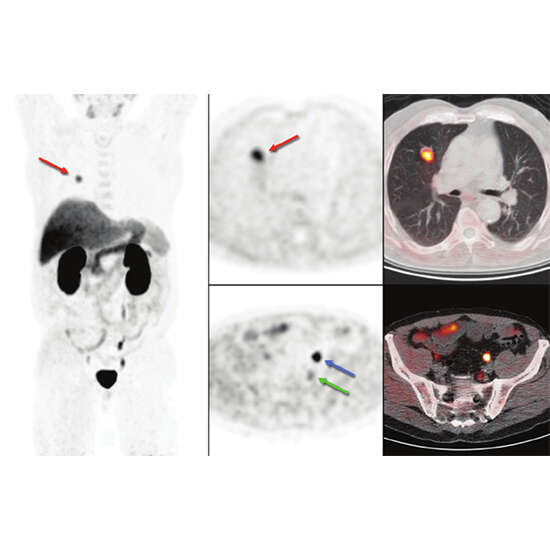

A PET (positron emission tomography) scan is known as an imaging procedure that uses the Choline F-18 to assess patients with the disease of prostate carcinoma. The Choline F-18 is a special chemical tracer that is also known as fluoromethylcholine-18. This scan would further help in detecting the location of the recurrent prostate cancer that also returned even after any successful treatment of the patient’s prostate cancer.

The 18 F-Choline PET/CT will be quite useful in the imaging modality in patients with any prostate carcinoma; it would further demonstrate the spread of your disease preoperatively along with the detection of the local recurrence after radical prostatectomy.

• This helps in detecting the spread of cancer before any surgical procedure or recurrence of the disease after the successful completion of radical prostatectomy.

• It is also useful in detecting the spread of cancer that is metastatic to distant sites such as lymph nodes, bone, soft tissues or the distant viscera.